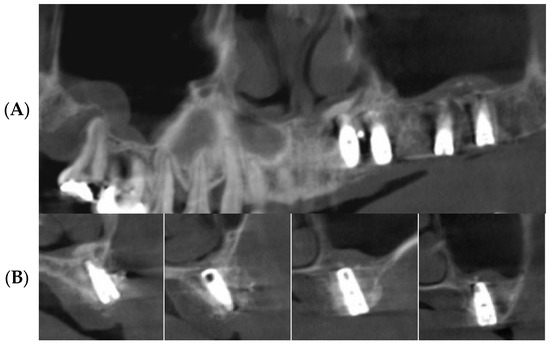

3.2. Radiographic Results